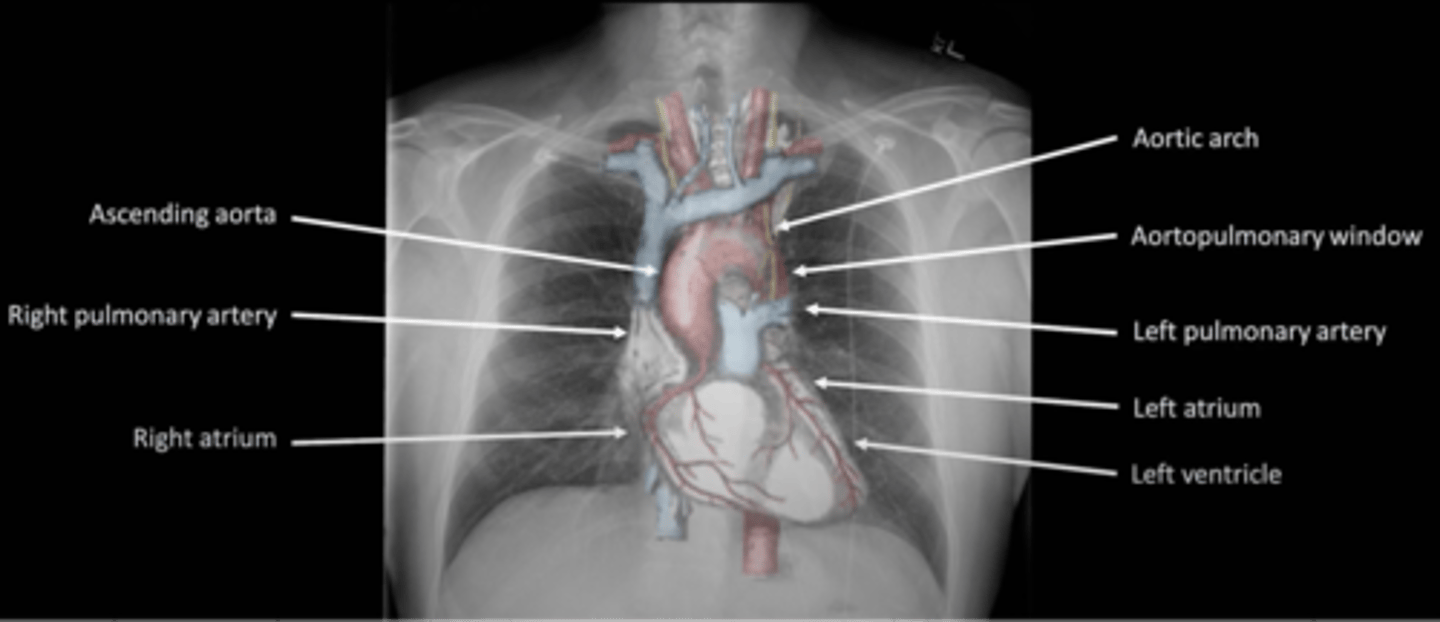

-are they in the correct location and the correct size

C: cardiac silhouette and mediastinum

-look for nodes or vasculature on the hila of both lungs

-left hila should be higher

H: Hila

-TB or sarcoidosis

What does bilateral hilar enlargment suggest

cancer

What does unilateral hilar enlargment suggest